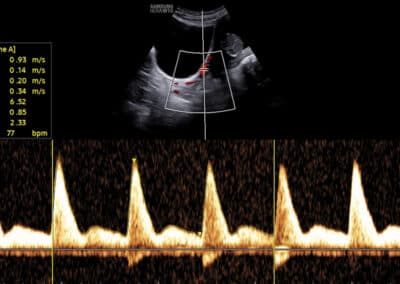

Dopplerovské vyšetření trojcípé srdeční chlopně – normální nález

Dopplerovské vyšetření trojcípé srdeční chlopně – trikuspidální regurgitace

UZ vyšetření trojcípé chlopně dle FMF protokolu

Podmínky FMF certifikace pro vyšetření trojcípé chlopně:

FMF certifikát na vyšetření NT (včetně absolvování on-line kurzu o vyšetření v 11.-14. týdnu těhotenství před získáním tohoto certifikátu) Úspěšné složení krátkého on-line testu týkajícího se hodnocení snímků zobrazujících vyšetření trikuspidální chlopně Zaslání tří snímků ze správného vyšetření trojcípé chlopně

Protokol pro správné vyšetření trojcípé chlopně:

CRL 45-84 mm (11-13+6 týden) Zvětšení (hrudník vyplňuje většinu obrazovky) Apikální čtyřdutinová projekce (hrot srdce směřuje směrem nahoru, ev. dolů na obrazovce) Gate 3mm přes trikuspidální chlopeň Odklon toku krve přes chlopeň 0-30º od vertikální osy Vysoká rychlost posunu křivky (2-3cm/s) Opakovat měření minimálně 3x Regurgitace na trojcípé chlopni je přítomna, pokud trvá minimálně polovinu systoly a její rychlost je vyšší než 60 (80) cm/s